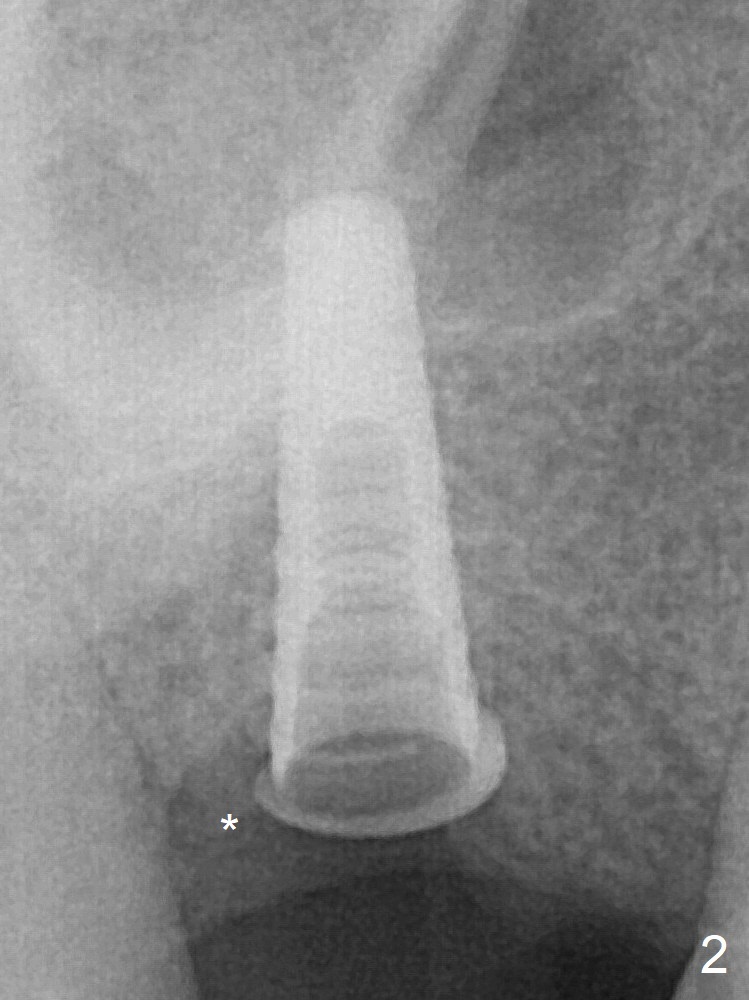

Following the last drill (3.8 mm) for 11 mm, a 4.5x11 mm dummy implant is placed 2 mm subgingival (Fig.2; *: space of the palatal socket). In fact the sinus lift is done by the implant, since the bone plug after Magic Drill is present in the apical portion of the osteotomy when the last drill is finished prior to implant placement. After the dummy implant is removed, the definitive one (the same size) is placed with >50 Ncm, followed by placement of a 4.5x4(3) mm abutment and VeraGraft mixed with autogenous one (Fig.3 *). VeraGraft granules are finer than Vanilla one (.25-1 mm vs. .5-1 mm).